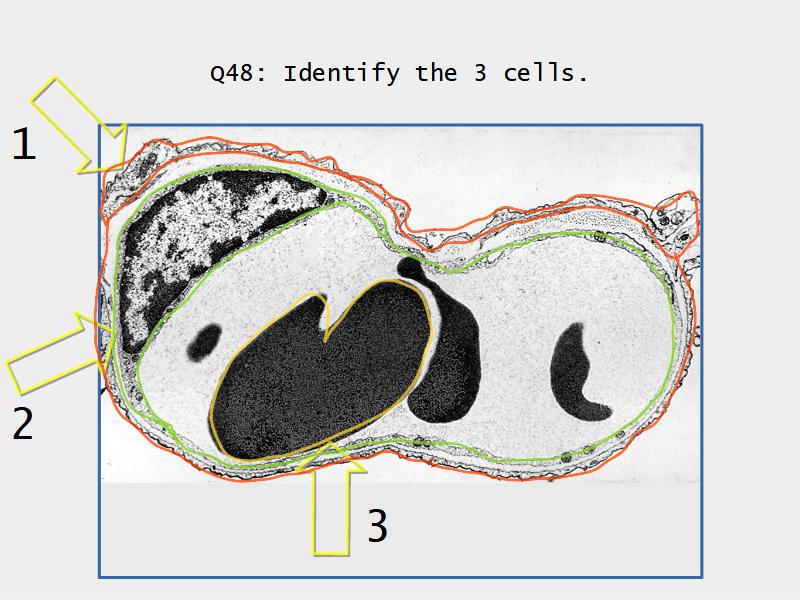

What cells are present?

Components of the Blood-Air Barrier?